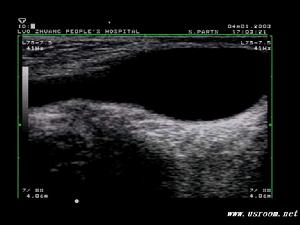

B超檢查可進一步明確診斷,對疑為睪丸腫瘤引起的繼發性睪丸鞘膜積液有重要意義、

B超檢查可進一步明確診斷,特別對疑為睪丸腫瘤引起的繼發性睪丸鞘膜積液有重要意義。

會陰部X線平片可確定鞘膜囊壁有無鈣化。鞘膜囊穿刺抽液後注造影劑攝片可檢查囊壁是否光滑,附睪、睪丸形態是否正常。超音波和放射性核素等檢查有助於確定陰囊內腫塊是囊性還是實性及睪丸、附睪有無病變。如果鞘膜內長期積液,內壓增高,而使睪丸缺血,睪丸生精功能不良,最終導致男性不育。